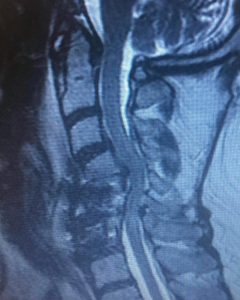

Kyphosis is the opposite of lordosis. Cervical means relating to the neck. While the human anatomy has curves, cervical kyphosis is either an abnormally straight neck spine or one that’s bent backward. The straighter or more pronounced the neck spine is, the more serious the condition tends to be with more side effects.

Here is an extreme example of a patient who came to me for correction of a previous attempt at surgery which failed to correct her severe Kyphosis and spinal cord compression. After the much more extensive surgery that I performed, she began to recover strength in her arms again and her ability to walk improved.